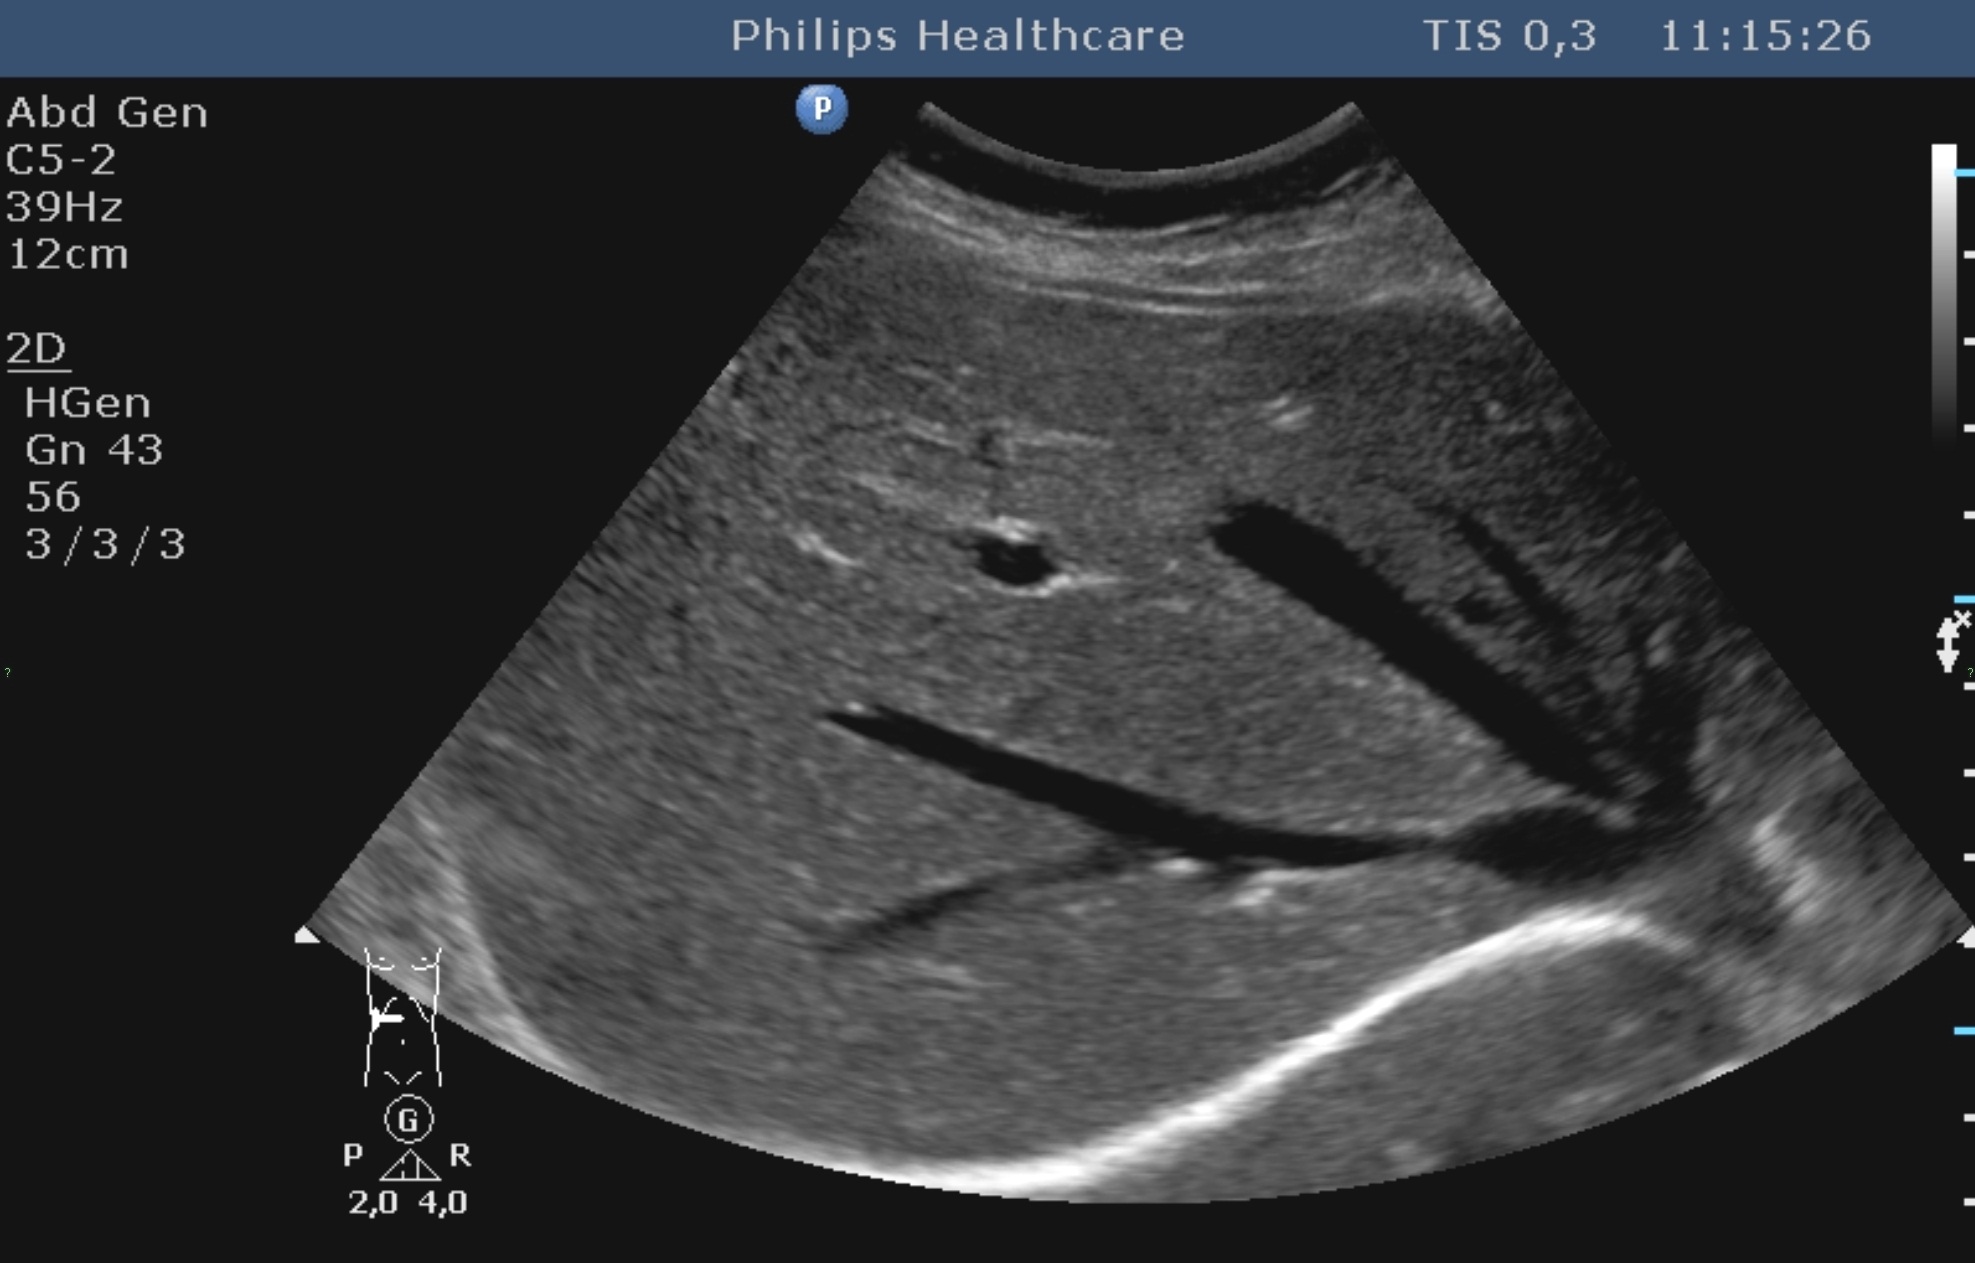

The echogenicity of the normal liver tissue is mildly hyperechoic (Figure 3) due to the intrahepatic connecting tissue structures, small veins, arteries and bile ducts (its echogenicity is principally comparable with the adjacent normal right kidney cortex, the liver has a bit hyperechoic structure than the right kidney, and its echogenecity is principally the same as the spleen's).

Figure 3: Normal liver, 2D US image

The portal vein and its branches have hyperechoic walls which can be easily differenciated in the liver structure. The walls of the hepatic vein branches have remarkable less echogenecity. The normal diameter intrahepatic bile ducts and the smaller liver arteries cannot be imaged and observed. The wall of the hepatic ducts and the main biliary duct (ductus choledochus) is also moderately hyperechoic. The hepatic hilum consists of the „double barrel” configuration (main biliary duct – portal vein, inbetween the cross-sectional view of the hepatic artery trunk) in the typical anatomical location, using an appropriate longitudinal plane.

The complex abdominal US examination is performed by a 3-5 MHz convex ultrasound probe, usually starting with the US imaging of the liver from subcostal direction in deep inspiration. In case of anatomical variations, upward displacement of the diaphragm, unappropriate breathing cooperation and postoperatively (eg., upper abdominal drain), the intercostalis imaging can be very important.